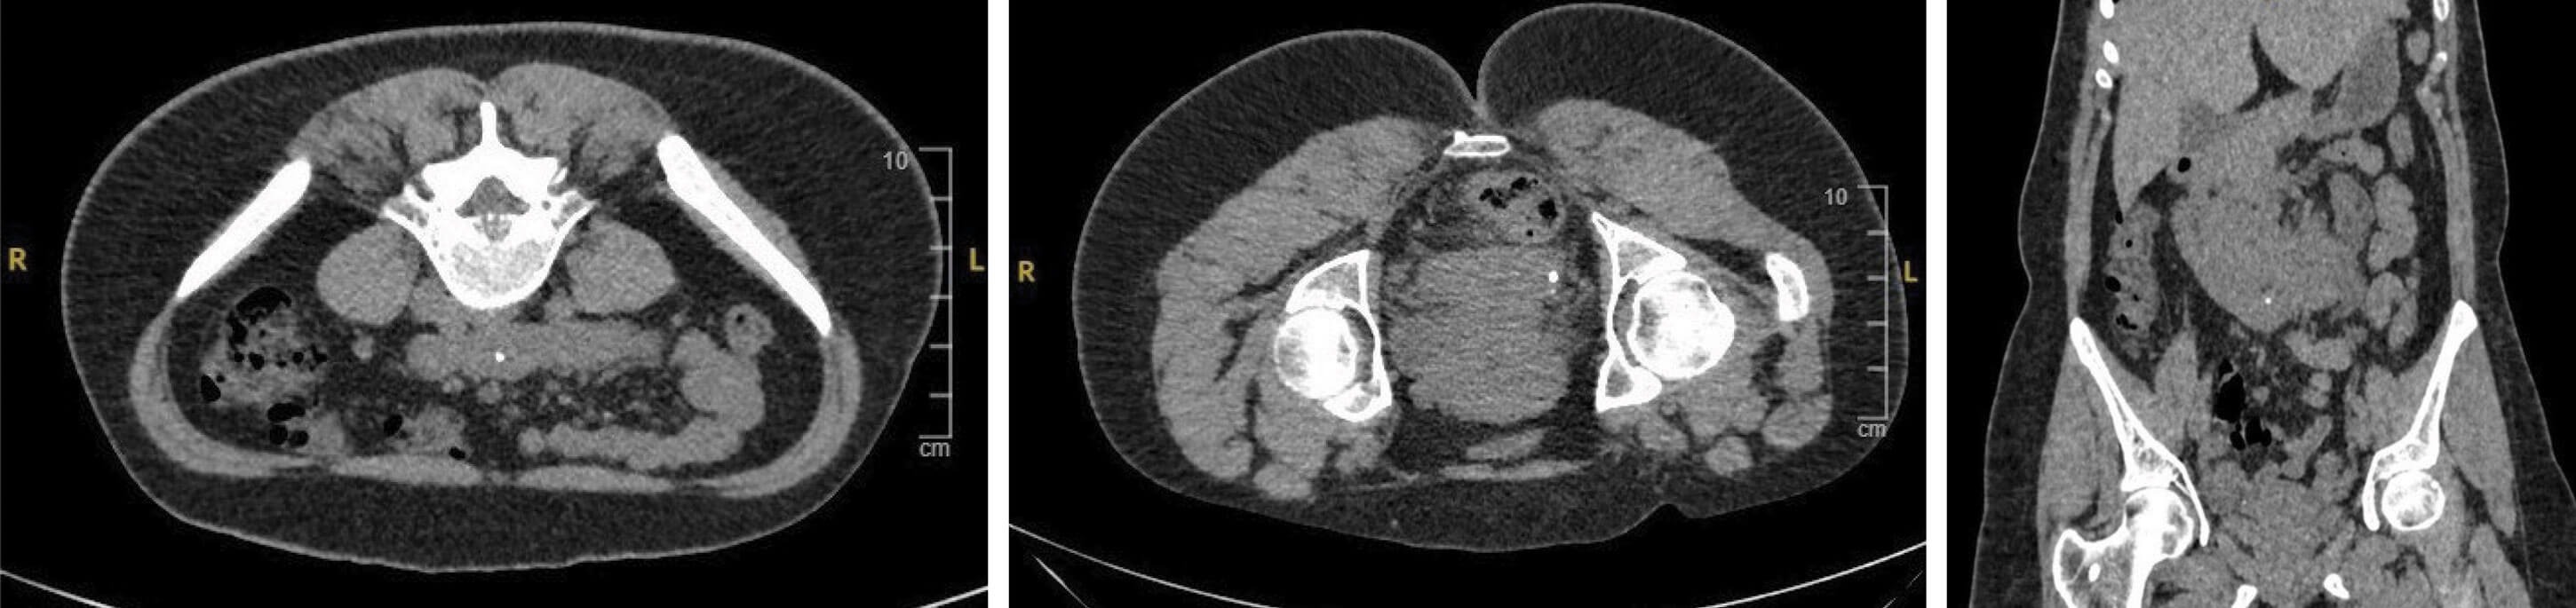

Figure 1.

- A 26-year-old female presents to A&E with loin pain. What do the CT images in Figures 1 (left, centre and right) show?

- Horseshoe kidney with a small stone in the renal pelvis and a ureteric stone.

- Horseshoe kidney has a population prevalence of 0.25%, being twice as common in men [1].

- The three most common pathologies are pelviureteric junction (PUJ) obstruction, stones and infection, while an increased incidence of injury in trauma is noted, as well as an increased risk of malignancies. Note that 30% remain asymptomatic and uncomplicated [3].